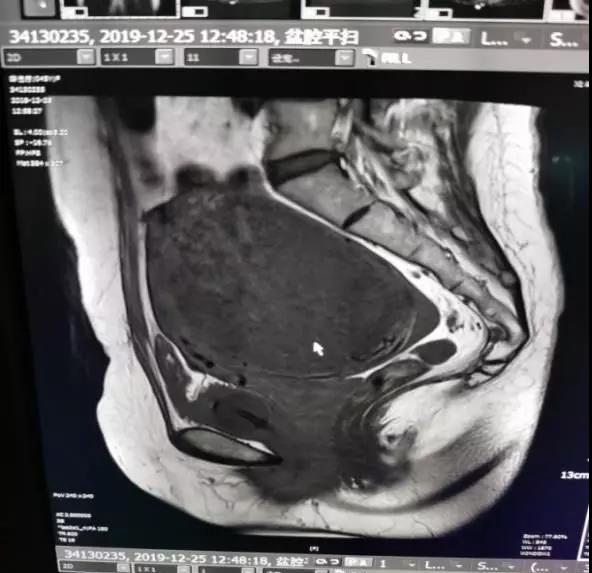

在了解病史后,醫(yī)護(hù)人員為李女士做了系統(tǒng)性的檢查,核磁共振結(jié)果顯示李女士體內(nèi)的子宮肌瘤已經(jīng)增大至10公分,且肌瘤位置較深,位于骶骨和恥骨聯(lián)合之間,壓迫膀胱和尿道,所以導(dǎo)致了急性尿潴留。